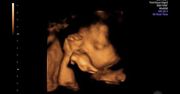

Podczas każdej wizyty pacjentka będzie miała mierzone ciśnienie, sprawdzany będzie również przyrost wagi. Pod koniec ciąży zalecane jest wykonanie zapisu KTG, przeprowadzanego co kilka dni, w celu sprawdzenia kondycji dziecka. Aby sprawdzić łożysko oraz zbadać prawidłową ilość wód płodowych zaleca się również badania USG. Warto przechowywać wyniki badań. Jeśli okaże się, że kobieta w ciąży musi zmienić lekarza lub trafić do szpitala, historię ciąży będzie można bez problemu odtworzyć. Oczywiście, jeśli zostaną zauważone jakieś niepokojące objawy, od razu należy udać się do ginekologa.